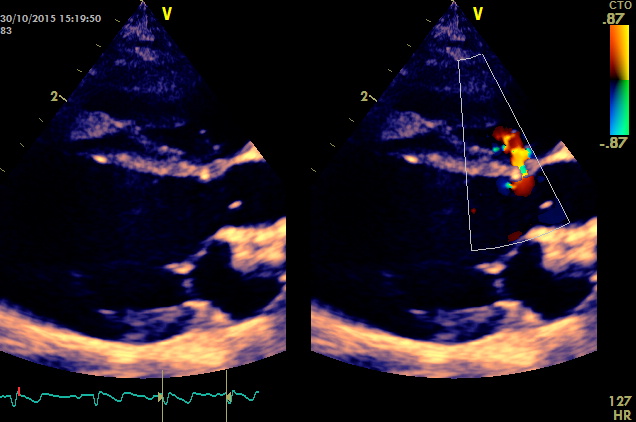

Questo e’ un caso classico che coinvolge la porzione perimembranosa ,la gravita’ del difetto e’ ovviamente proporzionale alla sua ampiezza ,in questo caso il difetto non supera i due millimetri i gradienti tra ventricolo sx e destro sono stimati dal doppler nella norma ,emodinamicamente non dovrebbe comportare lo sviluppo di sovraccarichi significativi del cuore sx . Diversamente i difetti piu’ ampi generano inevitabilmente overcirculation (per lo shunt sx destro emodidamicamente significativo) e sviluppo di scompenso cardiaco sx ,in alcuni casi oltre i due anni l’arteriopatia progressiva generata dall’overcirculation puo’ innalzare la pressione in polmonare e invertire lo shunt.

La diagnosi e’ stata eseguita solo a tre mesi ,la letteratura riporta rari casi di chiusura spontanea il soggetto ( buldog francese femmina di tre mesi) viene regolarmente monitorizzato.

nessuna evidenza di ingrandimento ventricolare